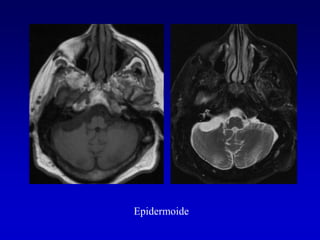

3 QUISTE EPIDERMOIDE

Epidermoide